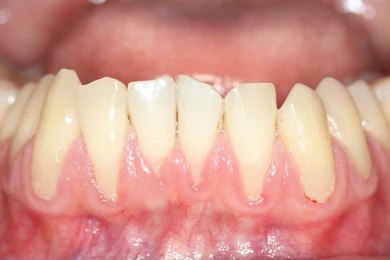

Receding gums medically known as gingival recession, occur when the gum tissue around the teeth wears away, exposing the tooth roots. This condition is becoming increasingly common, with studies showing that nearly 30% of adults over 30 experience some degree of gum recession. It often develops due to poor oral hygiene, aggressive brushing, gum disease or lifestyle factors such as smoking and hormonal changes.

It occurs when your gum margin surrounding the teeth wears away or pulls back. As a result, more of the tooth – or sometimes even the root – becomes visible.

Tooth roots are not protected by enamel like the crown of the tooth. Instead, they are covered by cementum, which is softer and more vulnerable. When receding gums expose these roots, sensitivity and decay become more likely.

- Noticeable root exposure

- Increased sensitivity

- Beginning of gum pockets

- Extensive root exposure

- Severe bone deterioration

- Loose teeth

- High risk of tooth loss